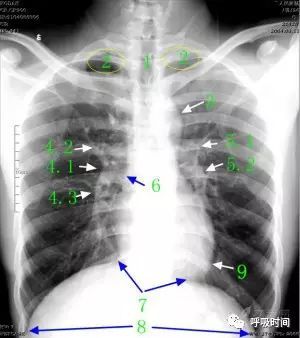

图 2 胸部正位片:1 气管;2 肺尖部;3 主动脉结